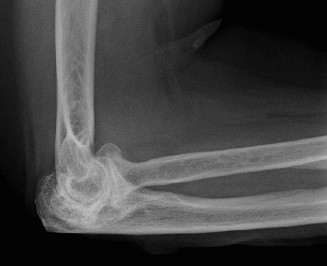

The pathological cascade in RA begins with synovial inflammation (synovitis), characterized by pannus formation, which invades and erodes articular cartilage and subchondral bone. This process, driven by inflammatory cytokines and proteases, leads to joint space narrowing, subchondral cysts, marginal erosions, and ultimately, osteolysis and capsular laxity. The typical presentation includes pain, swelling, stiffness, and progressive loss of motion, frequently progressing to fixed flexion deformities, valgus instability (due to radial head erosion and lateral collateral ligament attenuation), or less commonly, varus deformity. The ulnar nerve is particularly vulnerable to compression or traction neuropathy due to cubital tunnel involvement, tenosynovitis, or valgus deformity.

In RA, the synovial hypertrophy and effusion can directly impinge on nerves. Furthermore, bony erosions and progressive deformity can alter normal anatomical relationships, making surgical dissection more challenging. The radial head is frequently involved, leading to erosions and osteolysis, often resulting in radial head subluxation or dislocation and contributing to valgus instability. The olecranon and coronoid fossae can also undergo significant erosion, leading to bone loss.

The pathophysiology involves sustained synovial inflammation (pannus formation) that erodes articular cartilage, subchondral bone, and ultimately compromises ligamentous integrity. This leads to characteristic radiographic changes including joint space narrowing, subchondral cysts, marginal erosions, and osteopenia. Over time, these changes result in significant bone loss, joint subluxation, and debilitating deformity. The ulnar nerve is particularly vulnerable to compression or traction neuropathy due to synovitis, effusions, or progressive valgus deformity.

In RA, the articular surfaces of all three joints can be severely eroded. The radial head frequently undergoes significant osteolysis and erosion, leading to radial head subluxation or dislocation and contributing to valgus instability. The trochlear notch of the ulna and the olecranon process can also be significantly eroded, resulting in bone loss that complicates implant fixation during arthroplasty.

* Progressive joint destruction and deformity: Evidenced by advanced radiographic changes such as severe joint space narrowing, extensive erosions, subchondral cysts, significant osteolysis, or joint subluxation/dislocation. Common deformities include fixed flexion contracture (>30-45 degrees), severe valgus instability, or less commonly, varus deformity.

- Plain Radiographs: Anteroposterior (AP) and lateral views of the elbow are fundamental. Obtain true AP and lateral projections. Evaluate for characteristic RA changes: diffuse joint space narrowing, articular erosions (radial head, capitellum, trochlear notch, olecranon), subchondral cysts, osteopenia, and joint subluxation or dislocation. Assess overall bone stock, particularly at the distal humerus and proximal ulna, which is crucial for implant fixation. Stress radiographs may be considered to evaluate ligamentous instability if not readily apparent clinically.